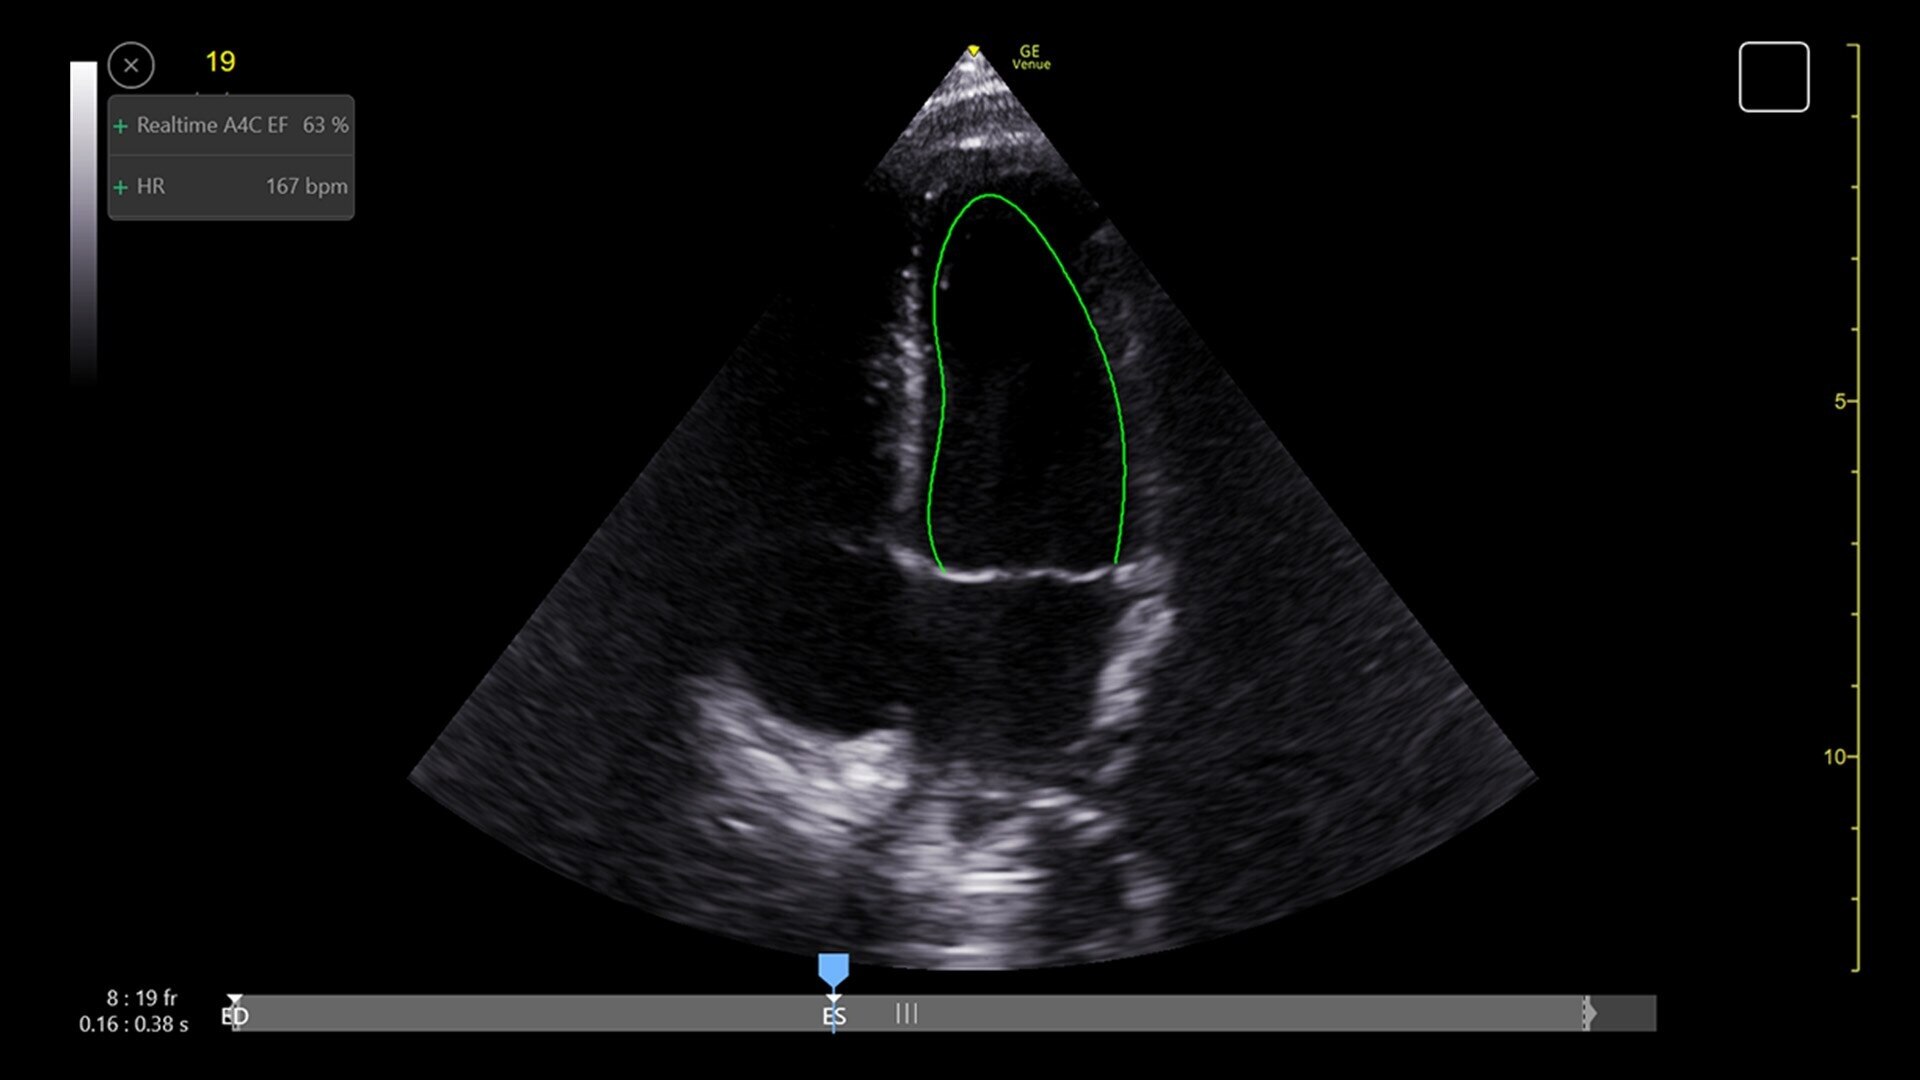

Simplify your workflow with AI-enabled clinical tools.

Helping drive consistency from user to user (whether one is an ultrasound novice or expert), Venue Fit features AI-enabled resources that help clinicians work smarter and more efficiently. Utilizing proprietary algorithms, we synthesize data from numerous patients to ensure accurate calculations for clinical confidence.